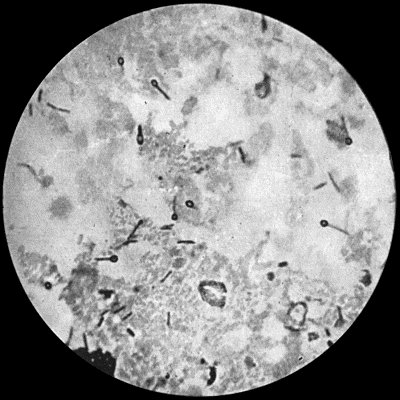

Fig. 4.—Bacillus coli communis in Urine, from a case of Cystitis. × 1000 diam. Leishman's stain.

Bacillus Coli Communis.—This organism, which is a normal inhabitant of the intestinal tract, shows a great tendency to invade any organ or tissue whose vitality is lowered. It is causatively associated with such conditions as peritonitis and peritoneal suppuration resulting from strangulated hernia, appendicitis, or perforation in any part of the alimentary canal. In cystitis, pyelitis, abscess of the kidney, suppuration in the bile-ducts or liver, and in many other abdominal conditions, it plays a most important part. The discharge from wounds infected by this organism has usually a fœtid, or even a fæcal odour, and often contains gases resulting from putrefaction.

It is a small rod-shaped organism with short flagellæ, which render it motile (Fig. 4). It closely resembles the typhoid bacillus, but is distinguished from it by its behaviour in artificial culture media.